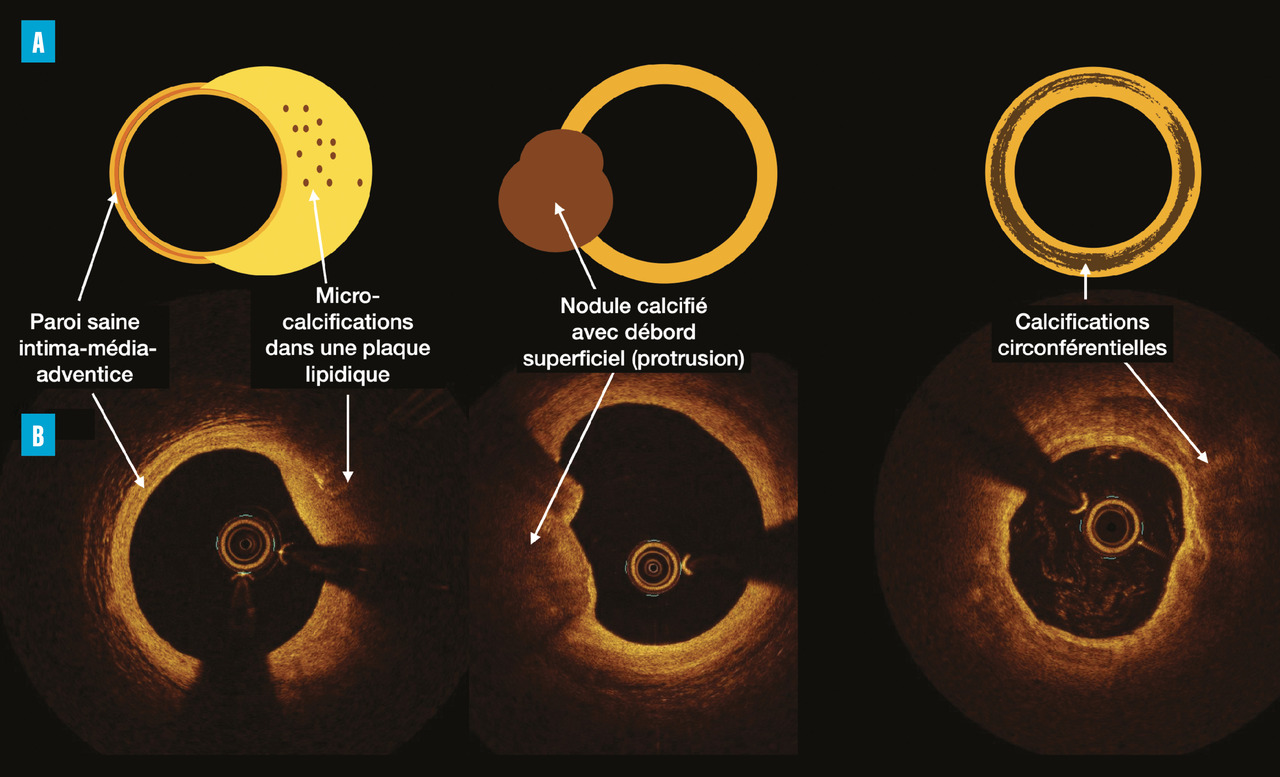

Sur le plan histologique, il est possible de classer les calcifications coronariennes en deux types :

– les microcalcifications (de 0,5 à 50 µm) apparaissent dans le noyau lipidique, sont typiquement liées au processus inflammatoire (présence de macrophages) et probablement impliquées dans la vulnérabilité de la plaque (ces microcalcifications peuvent être visibles en imagerie intracoronrienne mais ne sont pas appréhendées par le SC) ;

– les macrocalcifications (sous forme de nodule < 90° ou de calcification à extension circulaire > 90°) sont inversement corrélées avec les ruptures de plaque et donc classiquement associées à des plaques plus stables.

À cette catégorisation simpliste et fondée sur le volume, il faudrait ajouter des considérations de profondeur et de protrusion dans la lumière artérielle (pouvant entraîner une instabilité en provoquant des turbulences dans l’écoulement local du flux associées à une dysfonction endothéliale). Là encore, ces caractéristiques seulement partiellement accessibles par l’imagerie endoluminale (fig. 1 ) ne le sont certainement pas par le scanner.

À cette catégorisation simpliste et fondée sur le volume, il faudrait ajouter des considérations de profondeur et de protrusion dans la lumière artérielle (pouvant entraîner une instabilité en provoquant des turbulences dans l’écoulement local du flux associées à une dysfonction endothéliale). Là encore, ces caractéristiques seulement partiellement accessibles par l’imagerie endoluminale (